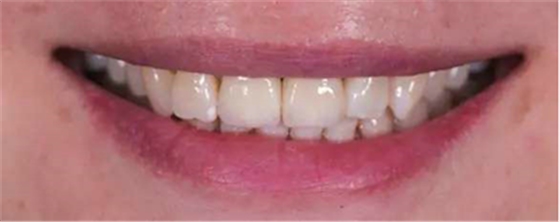

修復(fù)前

修復(fù)后

本病例中通過(guò)對(duì)患者修復(fù)體佩戴后的舌側(cè)、頰側(cè)、左側(cè)、右側(cè)以及微笑照的采集,充分展示修復(fù)體在口內(nèi)的佩戴情況,可以看到無(wú)論顏色還是與鄰牙的匹配適宜度都是非常高,也比較吻合年輕女性對(duì)美觀的要求。同時(shí),通過(guò)術(shù)后多次隨訪及跟蹤患者后期使用狀況,患者也對(duì)修復(fù)效果十分滿意。